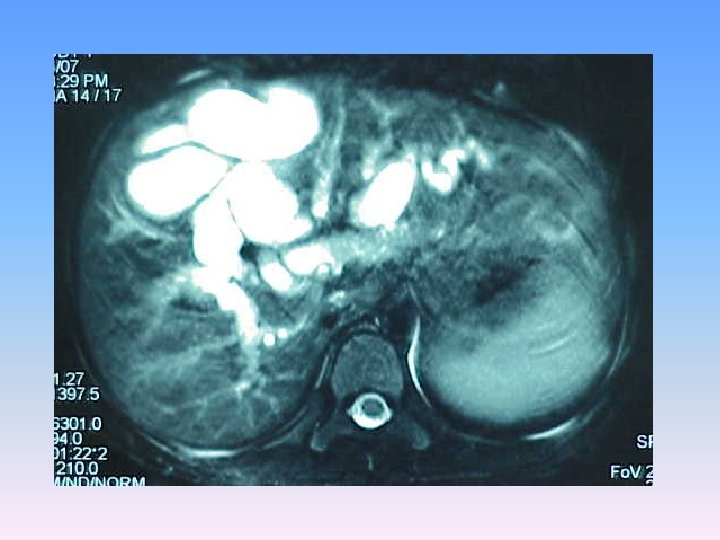

MRCP & MRI § Huge thicked wall cystic mass (140 x 120 mm), at the portahepatis that seems connected to biliary tree and gall bladder, resulted in severe dilatation of intra hepatic bile ducts and displaced right kidney posteriorly. § Spleen, kidneys, bowel loops and abdominal wall are normal. § Finding could be due to congenital anomalies like choledocal cyst, Duplication cyst, mesenteric cyst and hydatid cyst are in DDx.